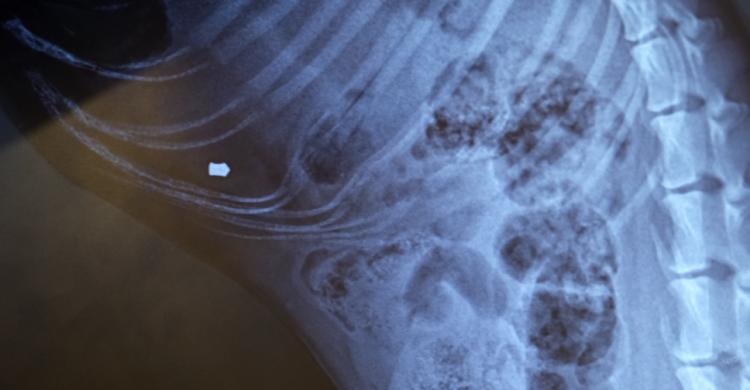

Після пострілів вдалося вижити лише 3 місячному цуценяті, куля потрапила у зону ребра, а от другій патрон потрапив прямо у серце. Від отриманого поранення собака померла на місці.